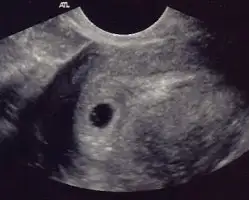

Benim 5+2 gun haftalık:

Harika bir görüntü yarın tam 5+0 olacağım ilk kez göreceğim umarım bende böyle bir görüntü ile karşılaşırım